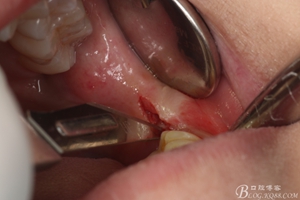

圖8. 翻瓣:建議翻小瓣

圖9.翻開瓣,可見38部分牙冠暴露